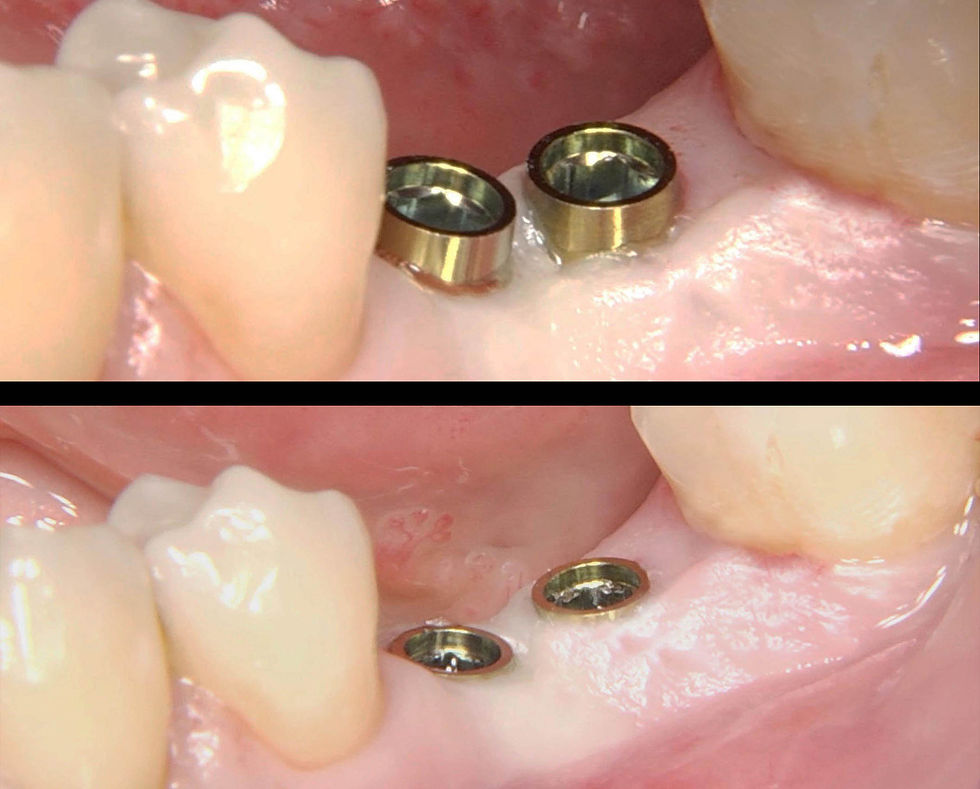

Impianti Prama in fase di inserimento e inseriti.